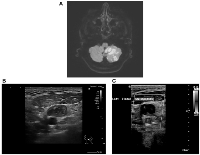

A chest X-ray showed no evidence of consolidation. Electrocardiography (ECG) revealed normal sinus rhythm, and a focused assessment with sonography for trauma (FAST) was negative. Given his neurological symptoms, an MRI of the brain was performed, which demonstrated multifocal acute infarctions in multiple vascular territories, most consistent with a cardioembolic event (Figure 1A).

Further Doppler ultrasonography on January 2, 2025, confirmed extensive deep vein thrombosis (DVT) in the left upper limb (Figure 1C). A repeat CT scan on January 9, 2025, showed significant progression of the mesenteric and para-aortic lymphadenopathy, reinforcing concerns for an underlying malignancy, particularly lymphoma. Additional findings included a newly identified splenic infarct and persistent renal infarcts. Pulmonary emboli were also noted, though of small volume.

Figure 1

Multi-modality imaging findings in a patient with Trousseau’s syndrome and metastatic colorectal cancer.

(A) Diffusion-weighted MRI of the brain demonstrating multifocal acute infarcts in multiple vascular territories, consistent with an embolic event. (B) Ultrasound of the neck revealing an enlarged supraclavicular lymph node with internal heterogeneity, raising suspicion for metastatic involvement. (C) Doppler ultrasound of the left neck demonstrating complete occlusion of the external jugular vein (EJV), consistent with malignancy-associated thrombosis.

Figure 1: Multi-modality imaging findings in a patient with Trousseau’s syndrome and metastatic colorectal cancer.